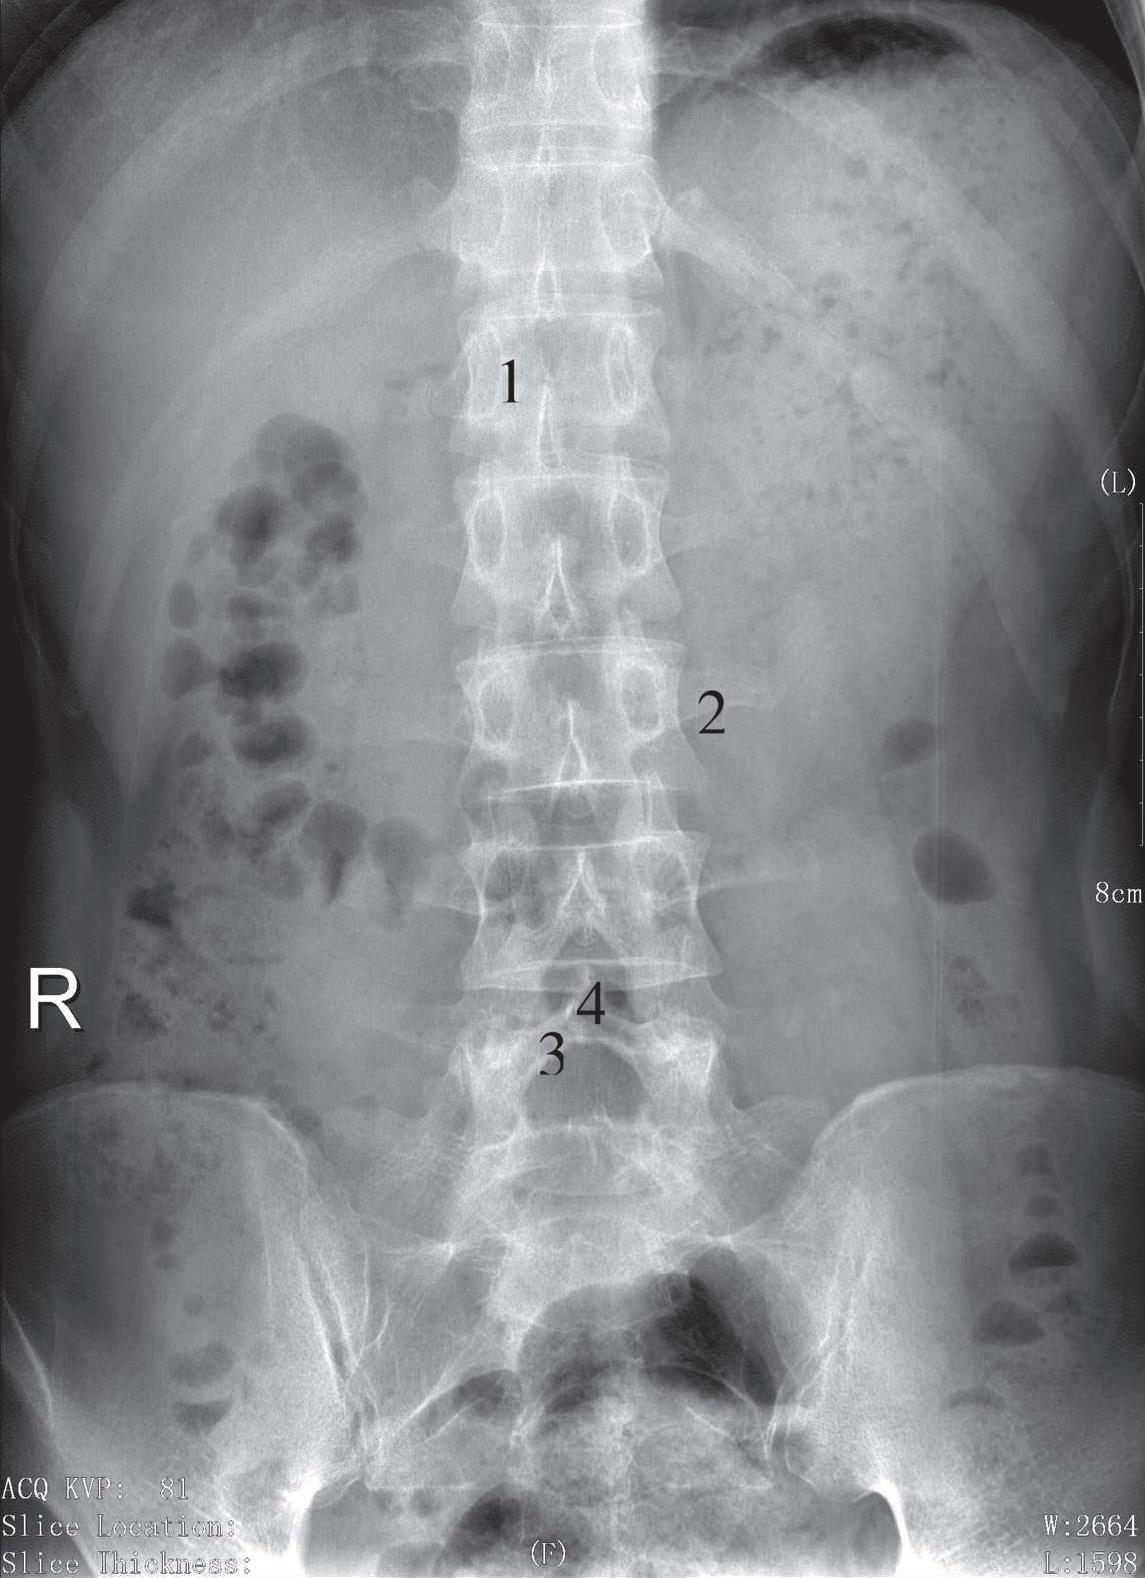

被检者仰卧于检查床上,身体正中矢状面对准检查床的中线,双下肢屈曲,双足踏于床面,使腰背部尽量贴近床面,两臂置于身旁或上举,影像接收器上缘包括T 11 ,下缘包括上部骶椎,两侧包括腰大肌,中心线对准L 3 (相当于脐上3cm处)垂直射入。影像显示T 11 ~S 2 的椎骨及两侧腰大肌,腰椎椎体为两侧稍凹的四方形,椎间隙显示清晰,两侧横突对称,L 3 横突较长,椎弓根、椎间关节、棘突亦显示清晰,各椎体骨小梁显示清晰,腰大肌及周围软组织层次可见(图3-13)。

1. L 1 椎体;2. L 3 椎体横突;3. 椎板;4. 棘突

图3-13 腰椎正位片